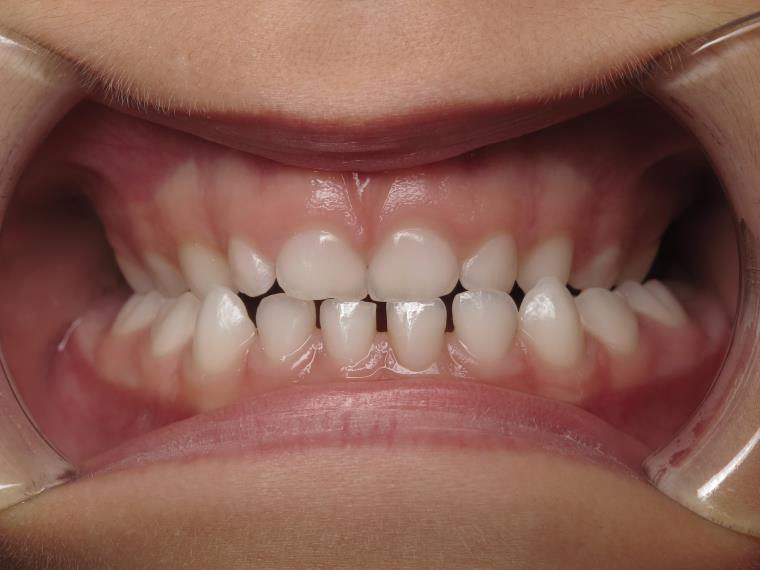

appareillage sectionnel multibagues pendant 18 mois